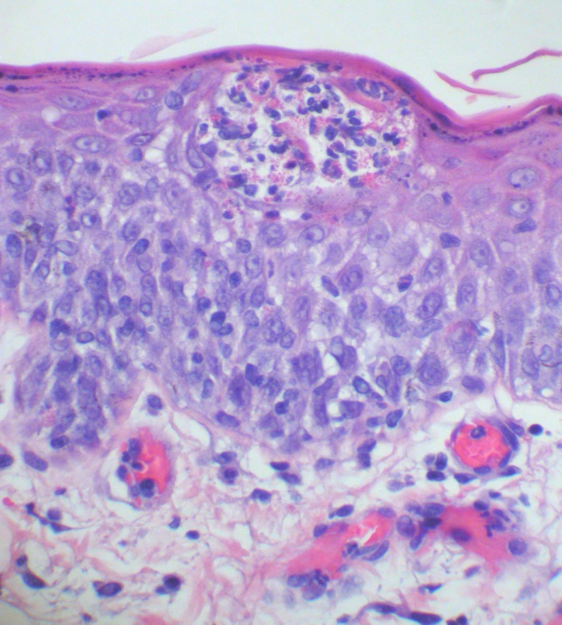

What is this?

What does it suggest?

Eosinophilic epidermal vesicopustules

Suggests direct aeroallergen contact

When it comes to histopath, PF is a ____ .

Subcorneal pustular acantholytic dermatitis